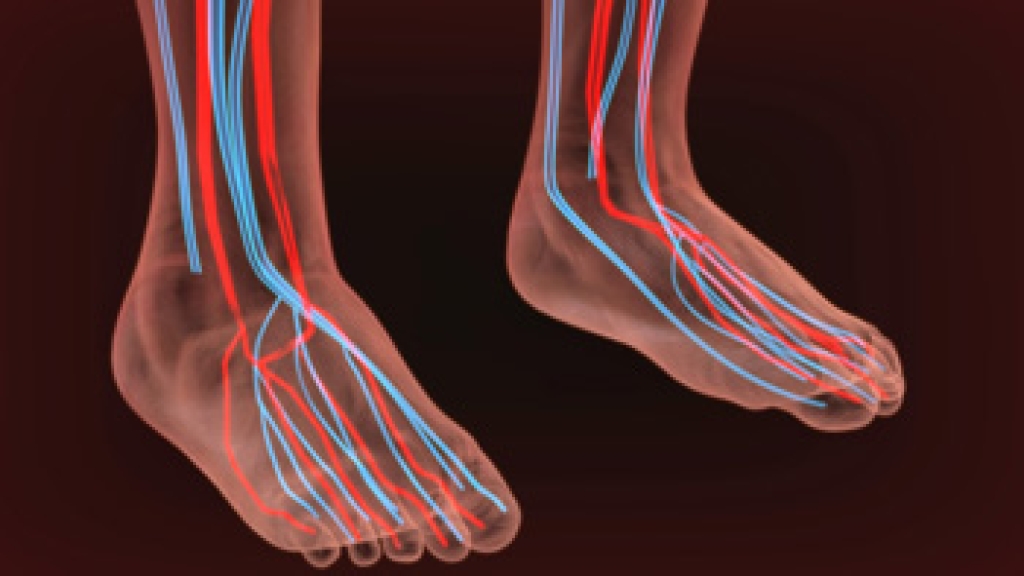

Symptoms and Causes of Poor Circulation in the Feet

Poor circulation in the feet is a condition where blood flow to the lower extremities is compromised, leading to various symptoms and potential health risks. One of the most common symptoms of poor circulation in the feet is persistent coldness, even when the weather is warm. Numbness and tingling sensations can also occur, making it uncomfortable to stand or walk. Swelling in the feet and ankles is another sign, as restricted blood flow can lead to fluid buildup. This condition can cause the feet to appear pale or bluish in color, and wounds or sores may take longer to heal. Muscle cramps and chronic foot pain, particularly during physical activity, can also be indicators of poor circulation. Several factors can contribute to poor circulation in the feet. Peripheral artery disease, or PAD, is a common cause, where atherosclerosis narrows the arteries and reduces blood flow. Conditions like diabetes can damage blood vessels, while smoking and obesity also can strain circulation. High blood pressure, a sedentary lifestyle, and blood clots can also hinder blood flow. If you have symptoms of poor circulation in your feet, it is suggested that you schedule an appointment with a podiatrist to identify the cause. Once that is determined, the proper treatment can be given for effective management and prevention of complications.

Poor circulation is a serious condition and needs immediate medical attention. If you have any concerns with poor circulation in your feet contact Steven Black, DPM of California . Our doctor will treat your foot and ankle needs.

Poor Circulation in the Feet

Poor blood circulation in the feet and legs is can be caused by peripheral artery disease (PAD), which is the result of a buildup of plaque in the arteries.

Plaque buildup or atherosclerosis results from excess calcium and cholesterol in the bloodstream. This can restrict the amount of blood which can flow through the arteries. Poor blood circulation in the feet and legs are sometimes caused by inflammation in the blood vessels, known as vasculitis.

Causes

Lack of oxygen and oxygen from poor blood circulation restricts muscle growth and development. It can also cause:

- Muscle pain, stiffness, or weakness

- Numbness or cramping in the legs

- Skin discoloration

- Slower nail & hair growth

- Erectile dysfunction

Those who have diabetes or smoke are at greatest risk for poor circulation, as are those who are over 50. If you have poor circulation in the feet and legs it may be caused by PAD and is important to make changes to your lifestyle in order to reduce risk of getting a heart attack or stroke. Exercise and maintaining a healthy lifestyle will dramatically improve conditions.

As always, see a podiatrist as he or she will assist in finding a regimen that suits you. A podiatrist can also prescribe you any needed medication.